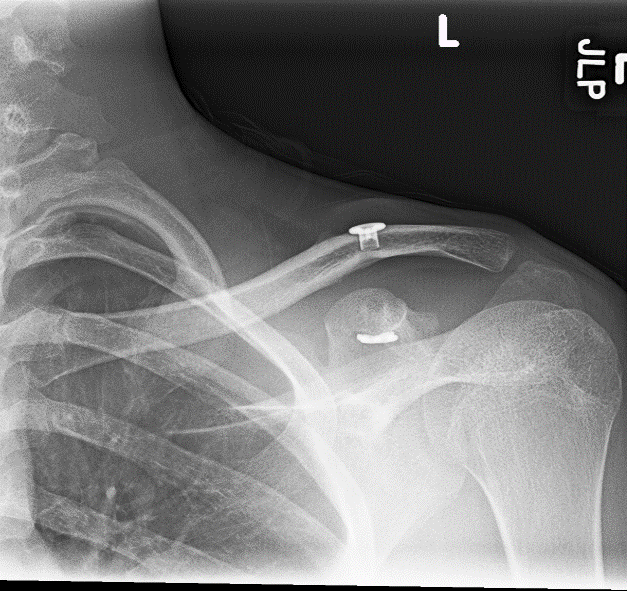

From casereports.bmj.com

Migration of a Kirschner wire into the lung with shoulder dislocation What Is Shoulder Separation Surgery It is a common injury that involves damage to the. Shoulder separations are acromioclavicular (ac) joint separations. A shoulder separation injury happens when trauma damages the ligaments around the. A separated shoulder, also known as acromioclavicular (ac) joint separation, occurs when the ligaments connecting your collarbone. A separated shoulder is also medically known as an acromioclavicular (ac) joint separation. It. What Is Shoulder Separation Surgery.